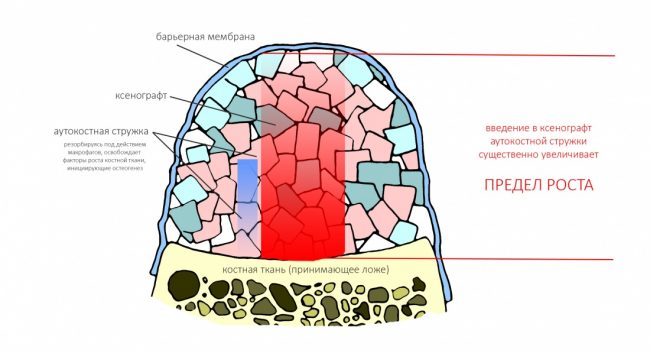

Вывод #1. У остеопластической операции с использованием чистых биоматериалов есть предел. Я называю его пределом роста. Он определяется скоростью и расстоянием миграции остеобластов и других клеток, участвующих в остеогенезе, ростом микрососудистого русла и т. д.:

Создание смешанного графта (т. е. введение в биоматериал аутокостной стружки) серьезно расширяет предел роста, но не преодолевает его. Причём, лишь небольшая (около 30%) аутокостной стружки участвует в регенерации, остальное «съедается» остеокластами и прочими макрофагами, при этом освобождаются т. н. «факторы роста» костной ткани — гормоноподобные вещества, инициирующие механизм остеогенеза: